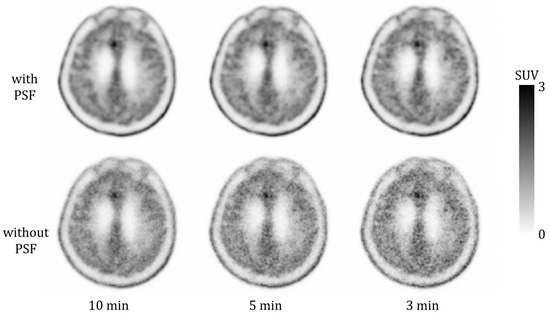

Shortened Acquisition Duration for Brain Tumor 11C-Methionine Positron Emission Tomography on Silicon Photomultiplier Positron Emission Tomography/Computed Tomography

by Takato Inomata, Kaoru Sato, Masanobu Ibaraki, Mamoru Kominami, Yuki Shinohara, Fumiko Kinoshita, Hiroyuki Yamamoto, Mamoru Kato, Toshibumi Kinoshita and Koichi Chida

Appl. Sci. 2025, 15(22), 12292; https://doi.org/10.3390/app152212292 - 19 Nov 2025

Positron emission tomography/computed tomography (PET/CT) scanners equipped with silicon photomultiplier detectors offer superior sensitivity and count-rate performance. The aim of this study was to evaluate the feasibility and impact of shortening the acquisition duration in brain tumor 11C-methionine PET using a silicon [...] Read more.

Positron emission tomography/computed tomography (PET/CT) scanners equipped with silicon photomultiplier detectors offer superior sensitivity and count-rate performance. The aim of this study was to evaluate the feasibility and impact of shortening the acquisition duration in brain tumor 11C-methionine PET using a silicon photomultiplier PET/CT system, and to assess how point spread function (PSF) correction influences quantitative values. In the phantom study, a brain tumor phantom was scanned using the Biograph Vision silicon photomultiplier-based PET/CT system. Data were acquired for 10, 5, 3, and 1 min, and the images were reconstructed with and without PSF correction. In the clinical study, 20 patients who underwent 11C-methionine PET were retrospectively analyzed. PET data were acquired over 10 min and subsequently reconstructed for 10, 5, and 3 min. We evaluated quantitative parameters including the maximum standardized uptake value (SUVmax), and their relative errors under shortened acquisition durations were analyzed. In the phantom study, the SUVmax increased with shorter acquisition durations; however, this increase was less pronounced with PSF correction. In the clinical study, relative errors of SUVmax for the 5 and 3 min acquisitions with PSF correction were 2.9 ± 3.8% and 5.2 ± 5.4%, respectively. They were smaller than those without PSF correction (5.5 ± 5.1% and 12.7 ± 8.5%), indicating superior quantitative stability with shortened acquisition duration. The combination of the Biograph Vision system and PSF correction enabled the acquisition of high-quality PET images with shortened scan times. Full article

Show Figures

Figure 1